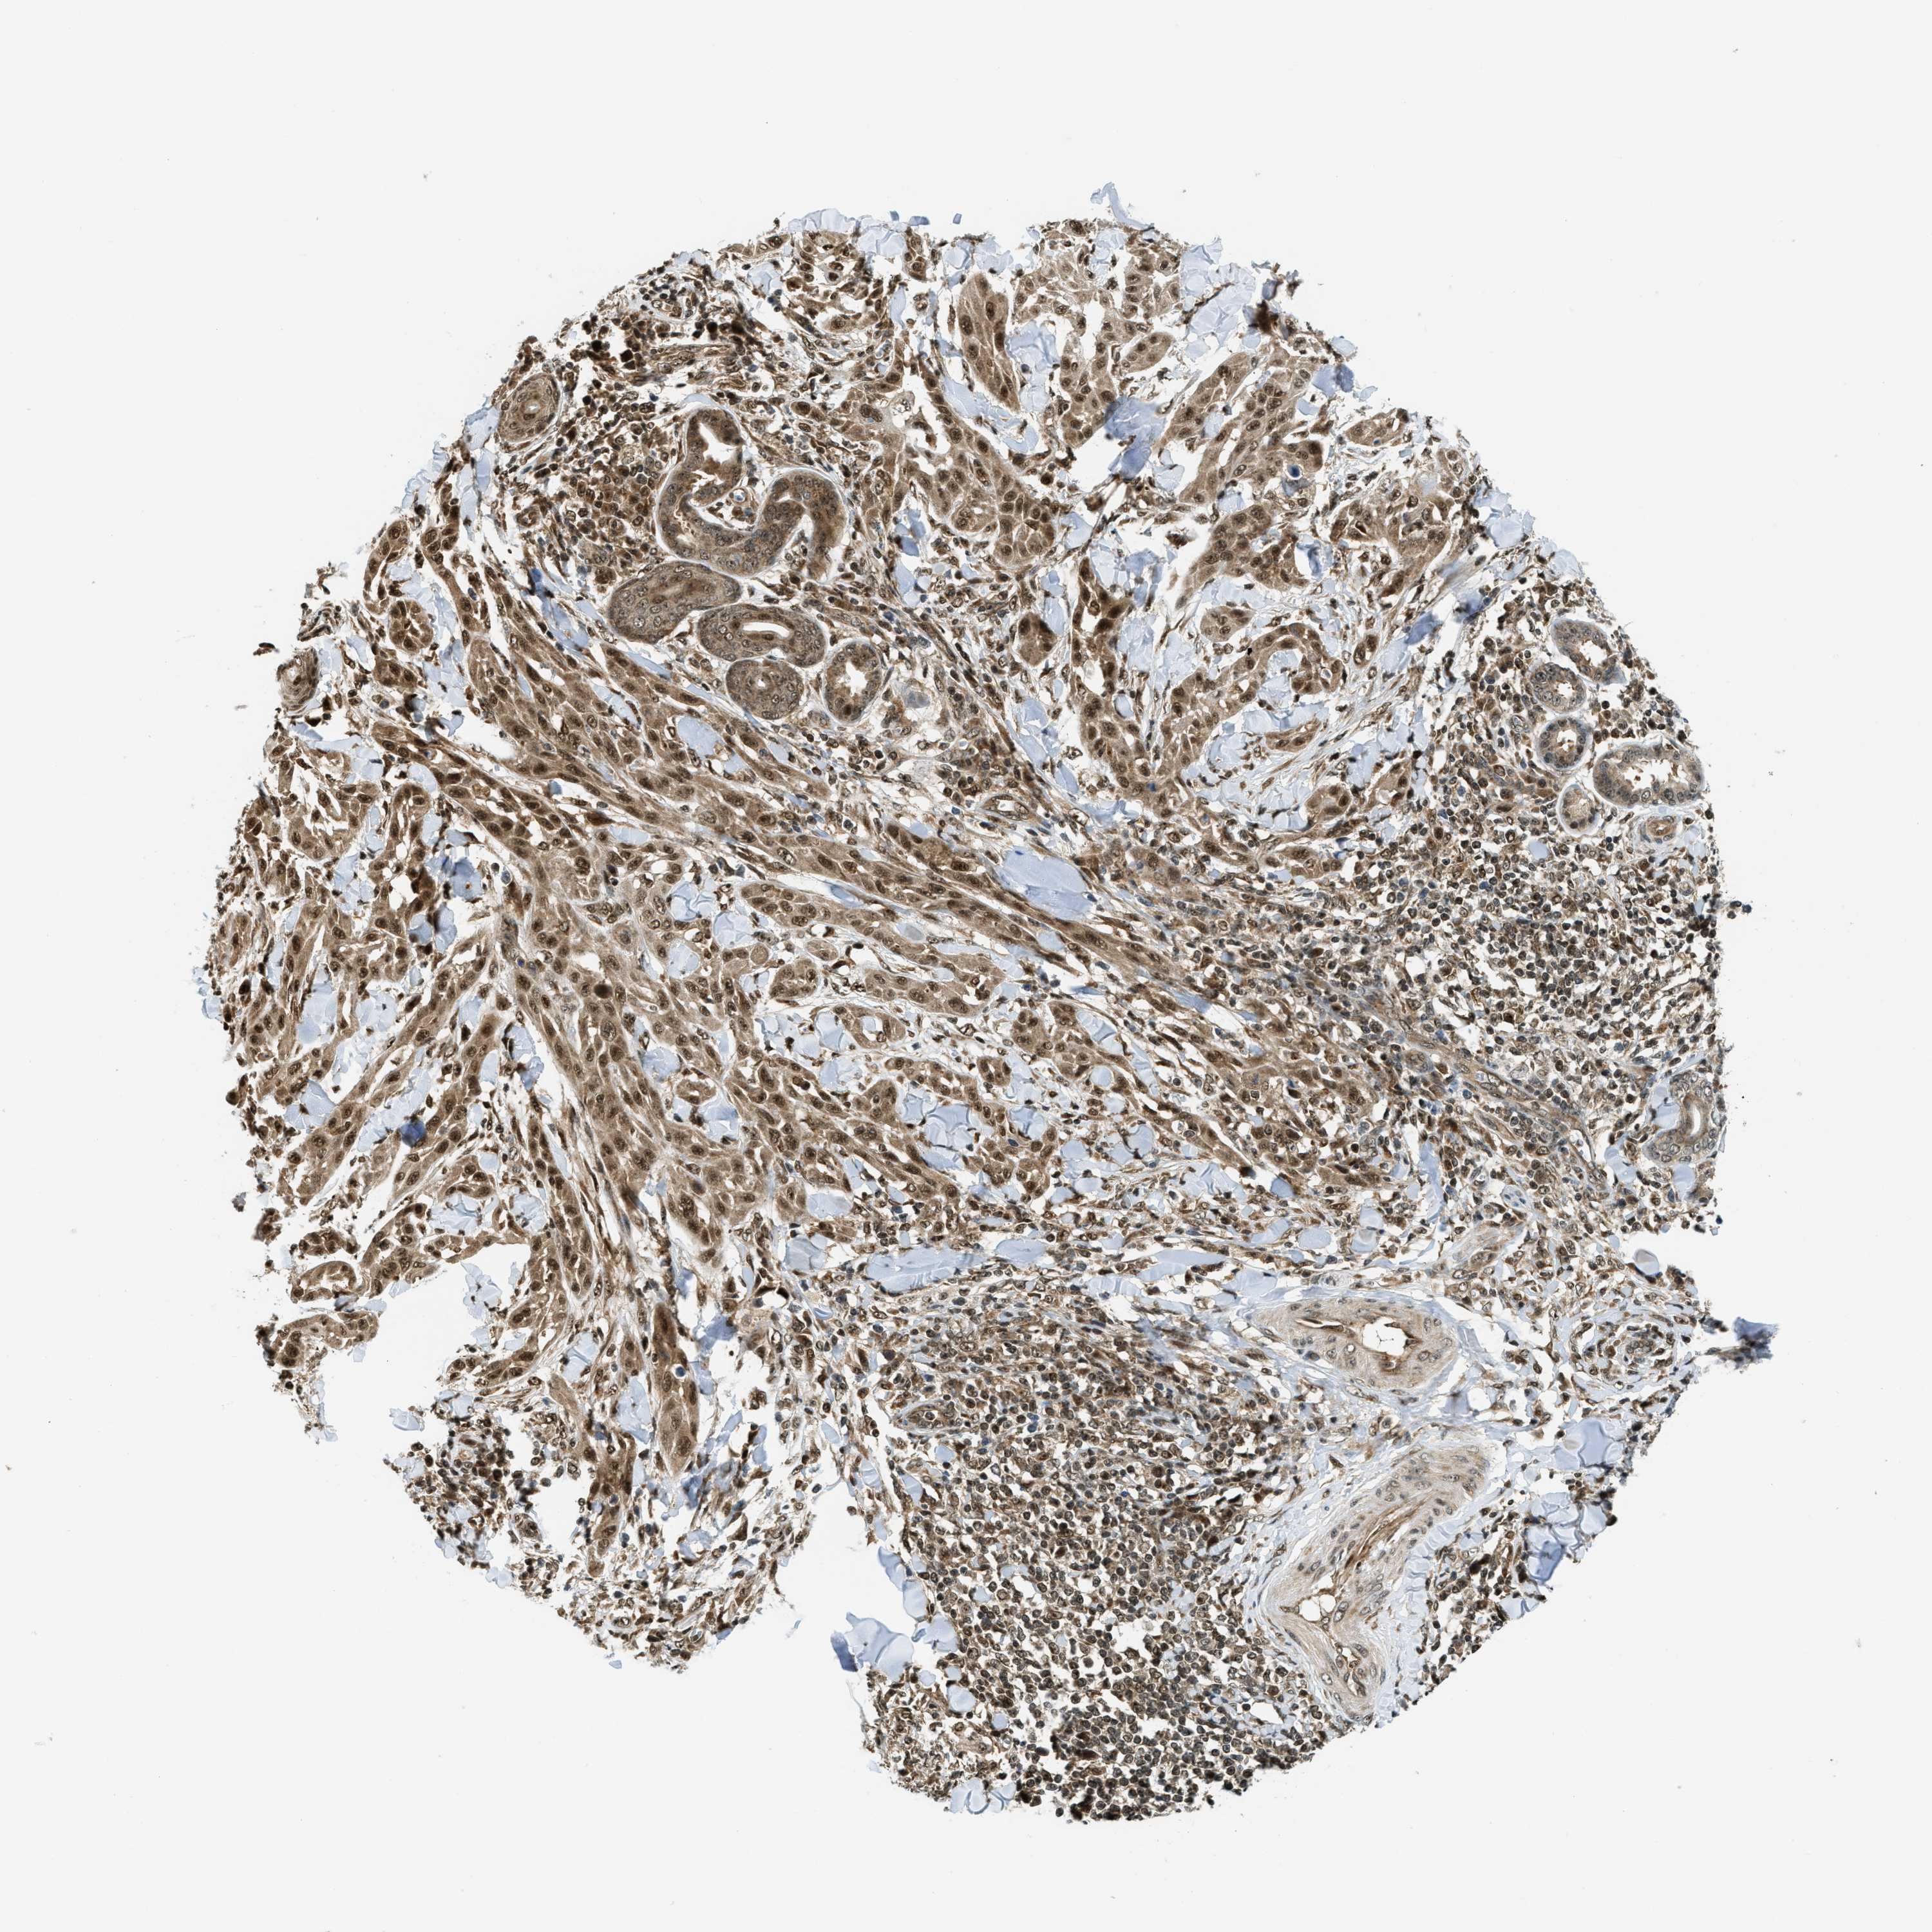

SKIN CANCER - Protein expressioni

A mouse-over function shows sample information and annotation data. Click on an image to view it in a full screen mode. Samples can be filtered based on level of antibody staining by selecting one or several of the following categories: high, medium, low and not detected. The assay and annotation is described here.

Antibody stainingi

Antibody staining in the annotated cell types in the current human tissue is reported as not detected, low, medium, or high, based on conventional immunohistochemistry profiling in selected tissues. This score is based on the combination of the staining intensity and fraction of stained cells.

Each image is clickable and will lead to virtual microscopy that enables deeper exploration of all samples and also displays staining intensity scores, fraction scores and subcellular localization as well as patient and tissue information for each sample.

Antibody CAB017041

Squamous cell carcinoma, NOS